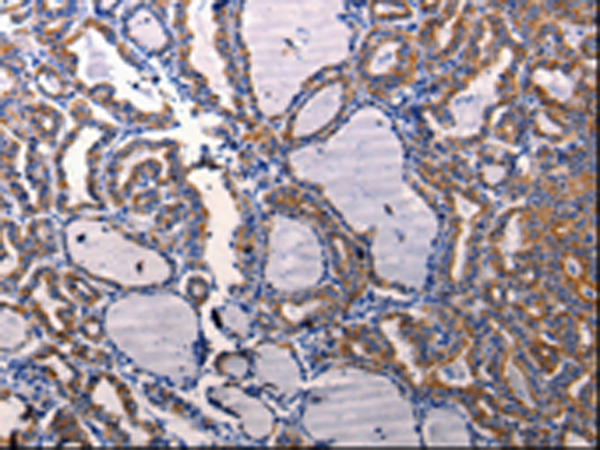

IHC 1/50-1/100 Human,Mouse,Rat

Researchers employ NDUFB9 antibodies in techniques such as Western blotting, immunohistochemistry (IHC), and immunofluorescence (IF) to assess protein expression, subcellular localization, and deficiencies in patient tissues or model organisms. These antibodies help identify mutations or dysregulation in NDUFB9. aiding in the diagnosis of mitochondrial disorders and mechanistic studies of metabolic reprogramming in tumors. Commercial NDUFB9 antibodies are typically validated for specificity using knockout controls or siRNA knockdowns, with reactivity across species like human, mouse, and rat.